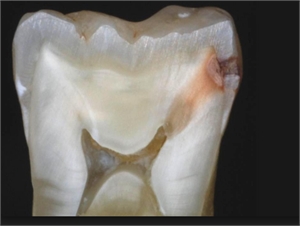

47+ Caries In Teeth Background. These are holes in the teeth. Tooth decay, also called dental caries disease, refers to demineralization or weakening of the teeth, and the end result of caries.

Dental caries, also known as tooth decay, is uncommon among companion animals. Dental caries (or tooth decay): It most often occurs in children and young adults, but it can tooth decay is a common cause of tooth loss in younger people.

Dental caries are also referred to as tooth decay or cavities.